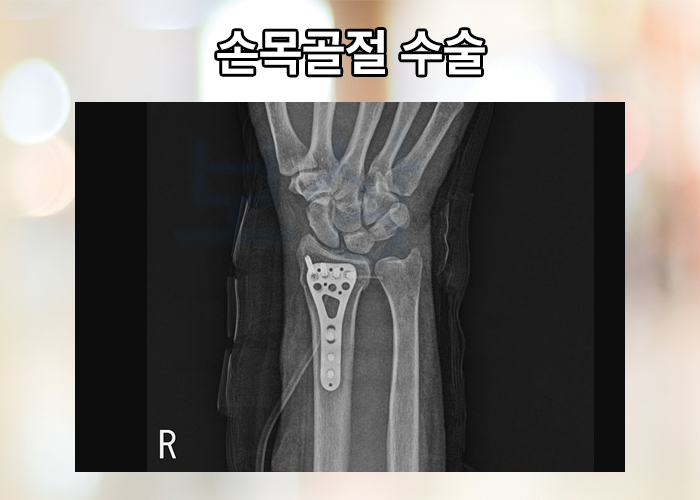

위와 같은 사고 경위로 발생하는 골절의 양상을 대부분 콜리스 골절 이라고도 하는데요, 손목이 골절되었을 경우 진단서 및 영상판독지를 보험회사에 제출하면 받을 수 있습니다. 골절 치료 목적으로 핀 삽입술 또는 금속판 고정술 등의 골절 치료 수술을 받은 경우 보험금을 받을 수 있습니다.

진단서, 수술확인서를 제출하시면 됩니다. 의료기관에 입원할 경우 하루당 일정 보험금 수령이 가능합니다. 진단서, 입퇴확인서를 제출하시면 됩니다. 치료 목적으로 발생하는 의료비에 대해 약관에 따라 보험금을 받을 수 있습니다.